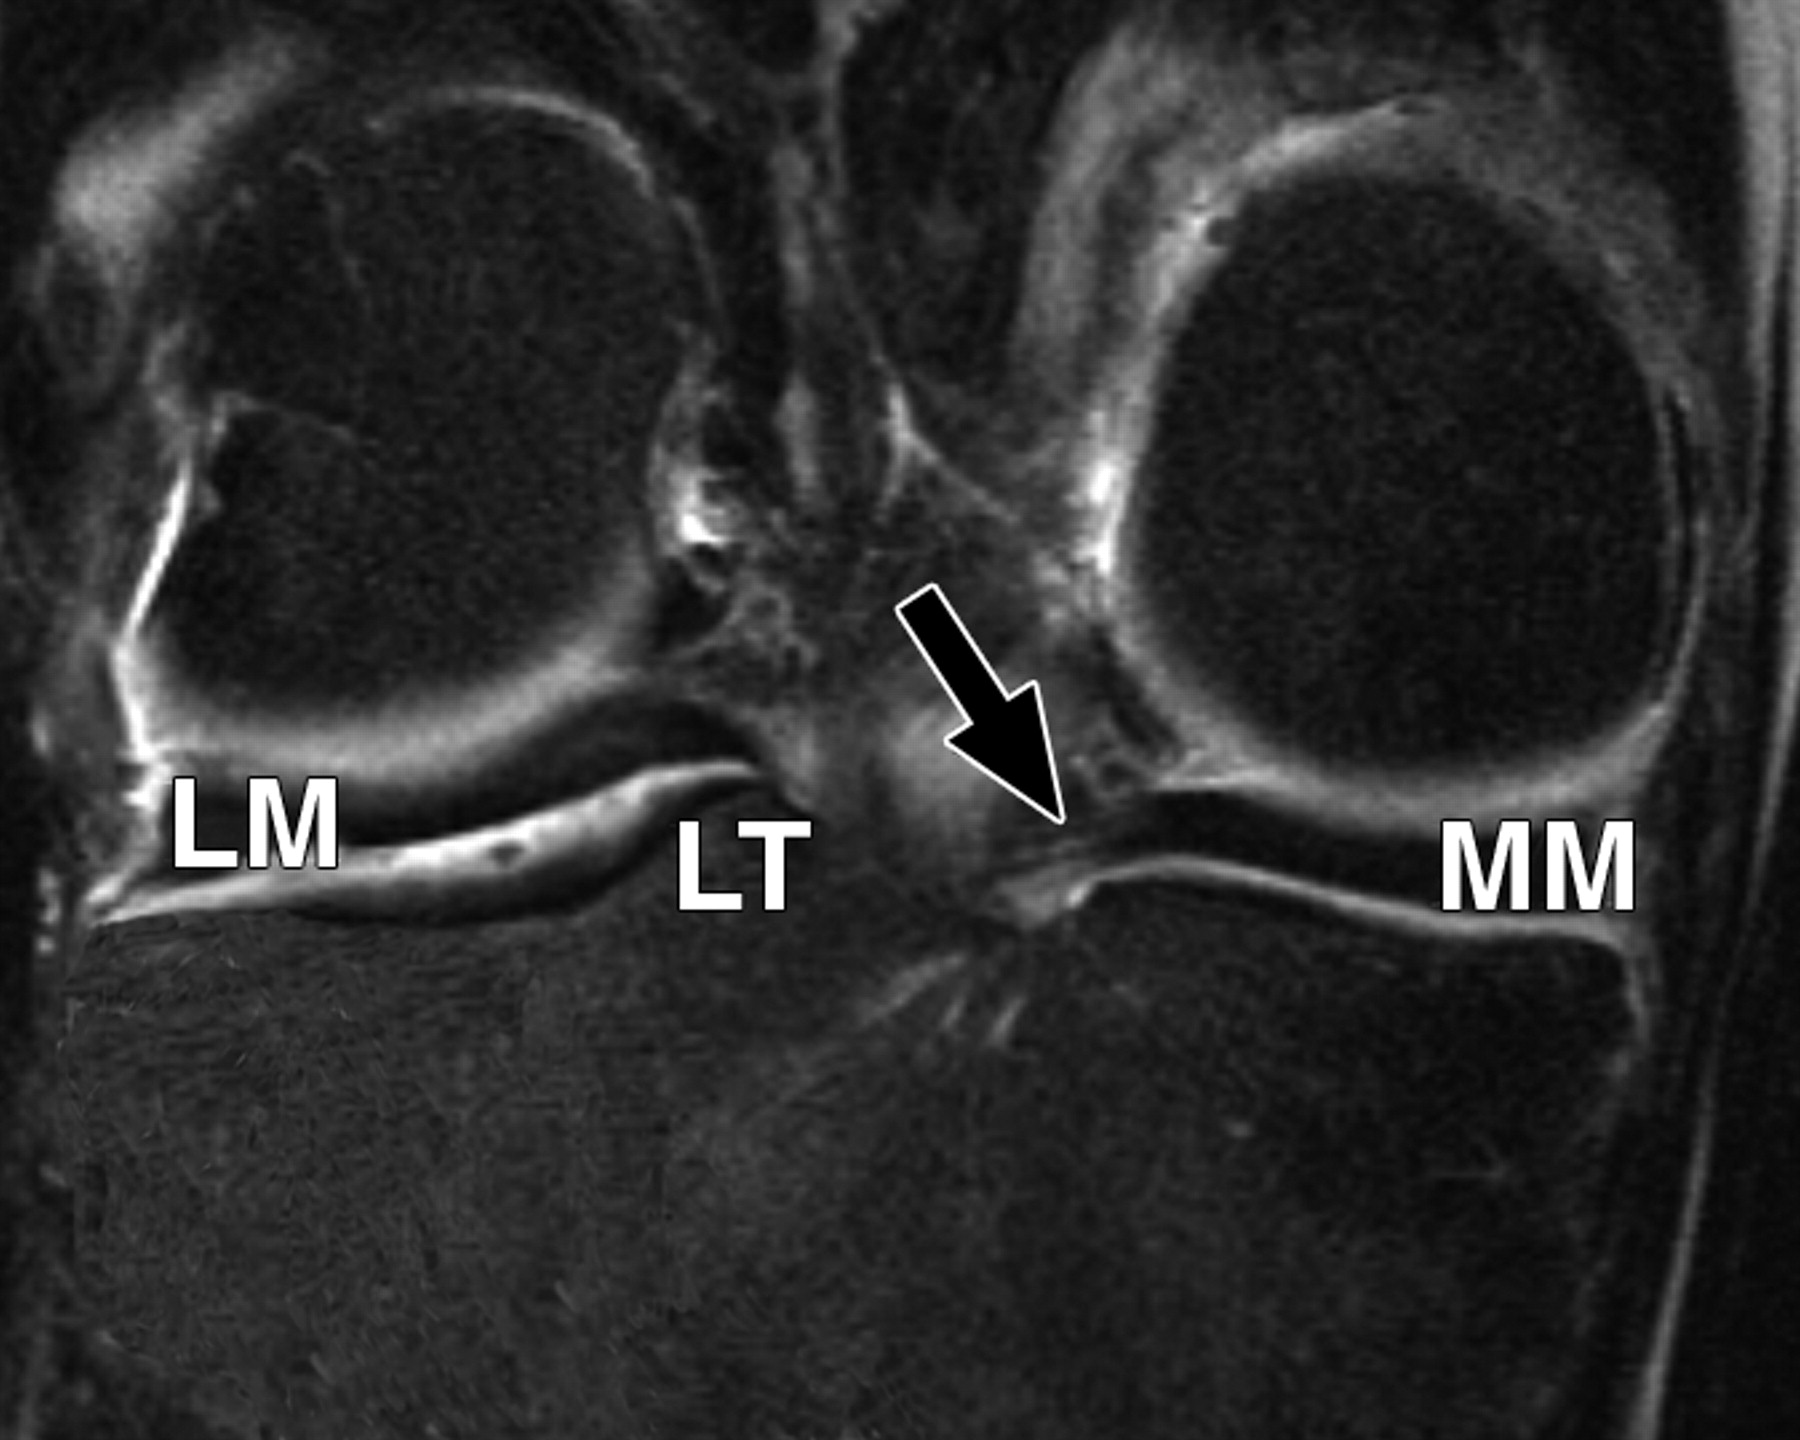

图5A-59岁男性。

中等加权、脂肪饱和、快速自旋回波(TR/TE有效值,3,700/29)3-T MR图像显示半月板后根和交叉韧带的解剖关系。

冠状面MR图像显示内侧半月板(MM)后根(箭头)覆盖后髁间区域的一个以上切片厚度。LM =外侧半月板。LT =胫骨外侧结节。

图5 B-59岁男性。中等加权、脂肪饱和、快速自旋回波(TR/TE有效值,3,700/29)3-T MR图像显示半月板后根和交叉韧带的解剖关系。

冠状面图像依次位于A的腹侧,显示外侧半月板后根(LM)(白色箭头)和内侧半月板后根(MM)(黑色箭头,B)的插入,覆盖后髁间区域的一个以上切片厚度。MT =胫骨内侧结节。